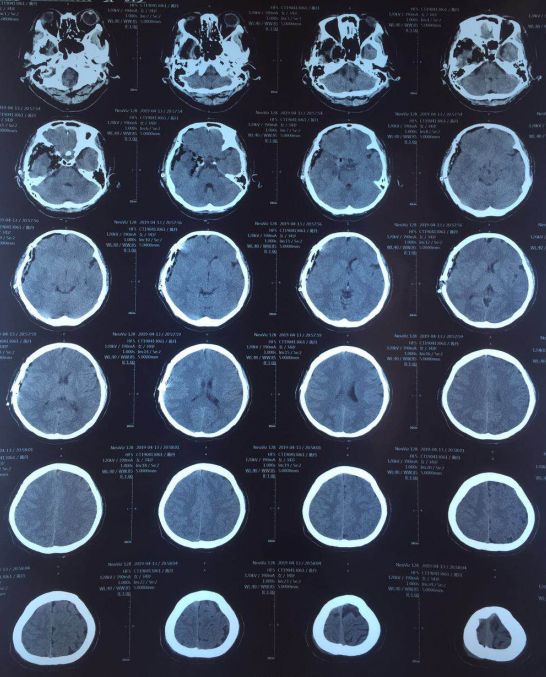

头CT:右侧海绵窦区可见类圆形高密度影,密度均匀,边缘较清晰,与正常组织界限清楚,考虑颅脑肿瘤可能性大。

术后复查头CT,颅内未见出血,中线居中,环池清楚。